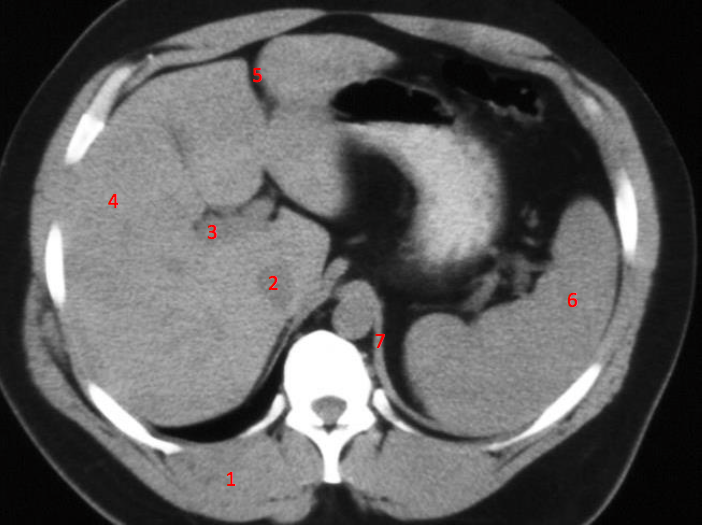

10

Number 8?

Descending colon

14

Number 4?

Rt diaghragmatic crus

16

Number 2?

IVC

17

Rt lobe liver

18

Number 1?

R lung

19

Rt lobe of liver

20

Number 6?

Stomach

32

Number 3?

Portal vein

33

Number 5?

Falciform/round ligament

34

Number 9?

Haematoma

35

Hepatic flexure

36

Superior mesenteric artery

39

Spleen

40

Number 7?

Lt iliac blade/ilium

41

L Ventricle

42

Rt psoas

43

Rt oblique muscle

44

Rt rectus abdonimalis muscle

45

Rt psoas muscle

47

Number 10?

Rt kidney

48

Duodendum

49

Aorta

52

Traumatic laceration of Lt kidney

53

Lt erectae spinae muscle

54